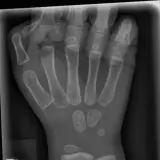

Over 2,100 interactive radiology cases, curated by radiologists for your level of training. Scroll, window, and view cases full screen — just like on PACS. Click linked findings in each writeup to jump straight to them on the image. Cases include sample reports, a focused discussion section, original illustrations, and videos.

完全交互式病例,配备您在 PACS 上期待的各项工具——滚动、调窗、缩放、平移、测量、ROI 和全屏模式。

丰富的标注直接在病例图像上突出关键发现。点击病例讲解中的关联发现,即可跳转至其在扫描上的精确位置。

交互式病例

像在工作站 PAC 上一样滚动、平移、调窗和缩放

通过标注的影像发现与示意图高效学习